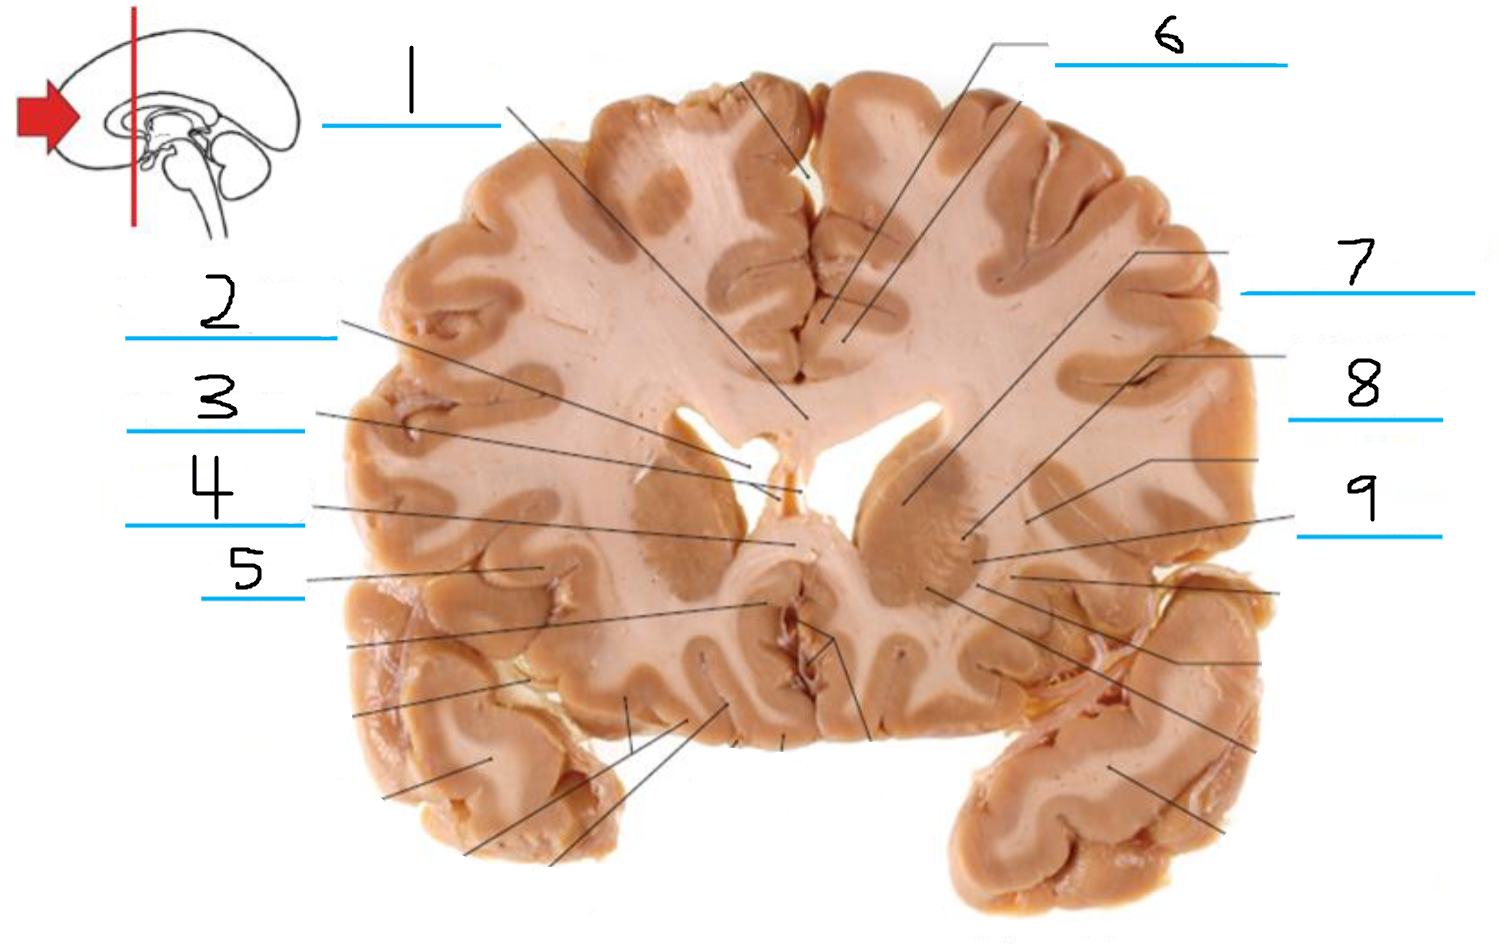

#1 is the:

Cingulate Gyrus

#2 is the:

Septum Pellucidum

#3 is the:

Lateral Ventricle

#4, #7, and #12 is the:

Fornix

#5 is the:

Third Ventricle

#6 is the:

Anterior Commissure

#8 and #11 is the:

Amygdala

#9 is the:

Hypothalamus

#10 is the:

Mammillary Body

#13 is the:

Insula

#14 is the:

Globus Pallidus

#15 is the:

Putamen

#16 is the:

Internal Capsule

#17 is the:

Caudate

#18 is the:

Corpus Callosum